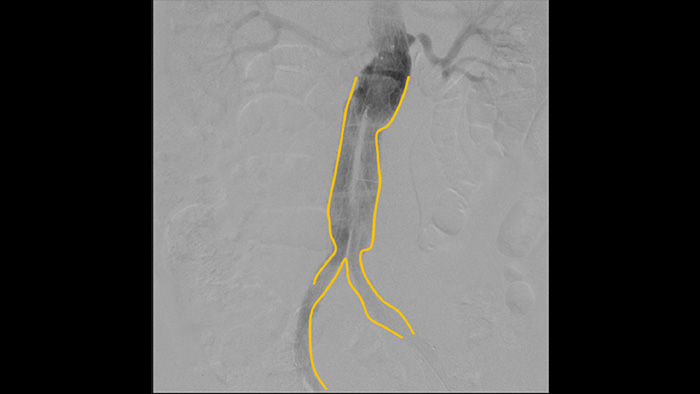

La angiografía por sustracción digital (ASD) se utiliza en procedimientos vasculares intervencionistas para ver con claridad los vasos sanguíneos mediante la eliminación de estructuras que pueden oscurecer la visibilidad de los vasos. La hoja de ruta de fluoroscopia superpone la imagen de contraste sustraída con anterioridad adquirida en la fluoroscopia en vivo, lo que le permite rastrear el dispositivo sin reinyectar el contraste.

Utilice la herramienta de contorno para marcar con facilidad una bifurcación o las ramas laterales solo dibujando en el monitor de la estación de visualización móvil con el dedo o con un ratón conectado externamente.